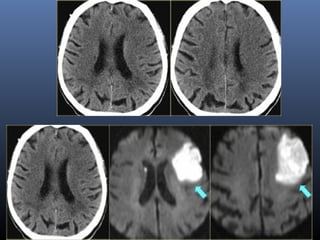

. Acute stroke (6 hours evolution) in a 46-year-old

woman with left hemiplegia. (a) Nonenhanced CT

scan shows the dot sign (arrow) in the right MCA, loss of

right-sided gray matter–white matter differentiation, and

obscuration of the basal ganglia

(b–e) Perfusion CT maps of MTT (b), CBF (c), and CBV (d) and a summary

map (e) show altered MTT and CBF in the right frontotemporal area, suggestive of

ischemia, and a small subcortical area with decreased CBV, suggestive of an

infarcted core. Note the area of increased CBF and CBV in the right caudate and

lenticular nucleus, representing the first stage of brain ischemia (compensatory

supply with cerebrovascular reserve). Thus the potential salvageable brain tissue is

equivalent to CBF minus CBV

Thus the potential salvageable brain tissue (green) is equivalent

to CBF minus CBV

Follow-up axial T2-weighted MR image shows a hyperintense right

front parietal area and caudate nucleus related to final infarction in the

ischemic area (both decreased and increased flow areas at perfusion CT),

which resulted because no treatment was performed